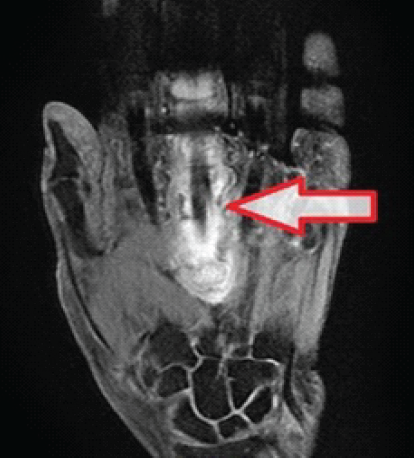

A 79-year-old female with no significant past medical history presented to our orthopedic clinic with a complaint of triggering and locking of her left middle finger. Her symptoms began 3 months prior with intermittent locking of the digit in flexion, which was initially painless. After being treated conservatively at another medical center, including a steroid injection around the A1 pulley, the patient experienced temporary relief. However, her symptoms recurred 2 weeks later, accompanied by increasing pain, swelling, and redness along the volar aspect of the finger. On physical examination, the patient had visible swelling and erythema over the volar side of the middle finger, extending from the proximal palmar crease to the proximal interphalangeal joint. There was a diffuse, palpable, tender mass along the flexor tendon, and the finger exhibited a non-reducible locking in flexion at the A1 pulley. The patient also had limited passive and active range of motion, with significant tenderness along the tendon sheath. Given the lack of response to conservative treatment and the presence of a palpable mass, a magnetic resonance imaging (MRI) of the hand was obtained. The MRI demonstrated severe distention of the flexor digitorum tendinous sheath of the middle finger, with a lobulated mass of heterogeneous tissue that was hyperintense on T2-weighted imaging and hypointense on T1-weighted imaging (Fig. 1).

Figure 1: Magnetic resonance imaging T2 coronal cut of the left hand showing severe distention of the third flexor digitorum tendinous sheath.

The surrounding soft-tissue edema further suggested an inflammatory or neoplastic process, and although tenosynovitis was initially considered, the possibility of a neoplastic etiology, such as a GCTTS, was raised.